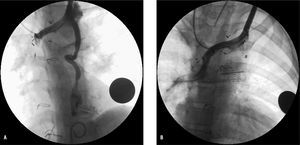

Un paciente con Glenn precisó embolización (con coils) de colaterales venosas desde la vena cava superior derecha al territorio de vena cava inferior, que mejoró su saturación del 75 al 84%; otra niña con Glenn desarrolló repermeabilización de una vena cava superior izquierda a seno coronario (embolización con dispositivo oclusor Amplatzer para ductus 6/4 por vía venosa anterógrada desde la vena femoral; fig. 4); en otro paciente con Glenn al que se había realizado fístula Blalock-Taussig izquierdo para favorecer el desarrollo de su arteria pulmonar izquierda, que presentaba hipoplasia importante, ésta fue posteriormente embolizada con oclusor Amplatzer para ductus 6/4 al completar el Fontan.

Fig. 4. A: angiografía en vena innominada en paciente con Glenn, que muestra repermeabilización de una vena cava superior izquierda a seno coronario. B: angiografía en vena innominada tras embolización con dispositivo oclusor Amplatz para ductus 6/4, implantado desde vena femoral mediante asa venovenosa.

El desarrollo de colaterales venosas o la recanalización de conexiones embriológicas desde el territorio de la vena cava superior son complicaciones descritas tras la cirugía tipo Glenn27, más frecuentes en los pacientes con gradiente transpulmonar (resistencia arteriolar pulmonar, es decir, diferencia entre la presión pulmonar media y la presión media de la aurícula izquierda) más elevado28, que en ocasiones puede precisar embolización al causar hipoxemia significativa, como ocurrió en 2 de nuestros pacientes.